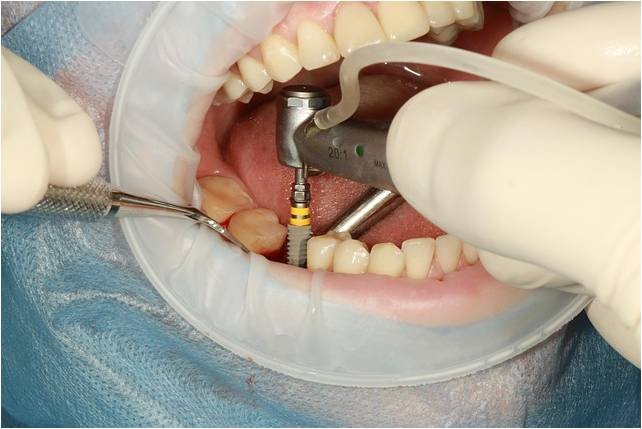

Implante

Planejamento e estudo de caso para o melhor tratamento, incluindo reposição de massa óssea

Quando fazer um implante?

Faça um implante dentário quando houver perda de um ou mais dentes devido a acidentes, doenças periodontais, cáries, infecções ou bruxismo. É indicado também para quem tem próteses desconfortáveis ou soltas, ou deseja melhorar a aparência e a mastigação. O dentista é o profissional responsável por avaliar a necessidade do implante após analisar a saúde geral e bucal do paciente.